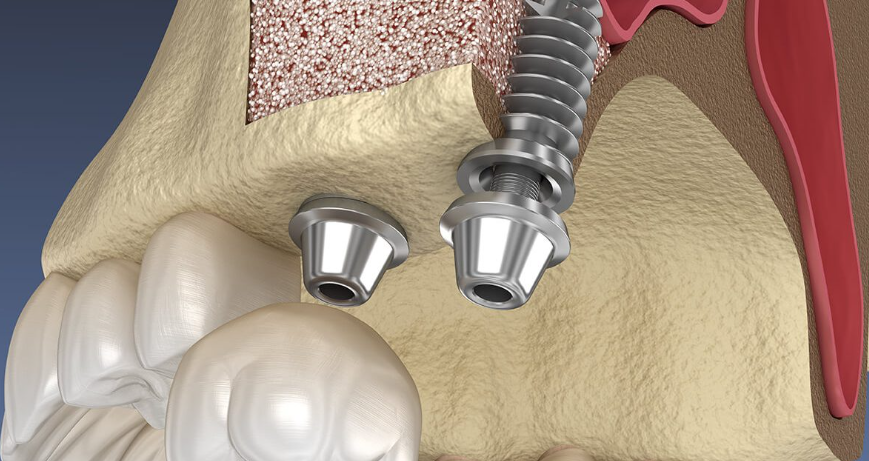

زراعة الأسنان

المعيار الذهبي لتعويض الأسنان

زراعات أسنان متطورة تبدو وتشعر وتعمل كالأسنان الطبيعية. من تعويض سن واحد إلى إعادة تأهيل الفك الكامل.

AlfaGate Dental Implants Collection

زرعات فردية

زرعات تيتانيوم فردية لتعويض سن واحد مفقود

جسور على زرعات

تعويض عدة أسنان بجسور مدعومة بزرعات

All-on-4

استعادة الفك الكامل بأربع زرعات موضوعة بشكل استراتيجي

All-on-6

ثبات معزز بست زرعات لدعم الفك الكامل